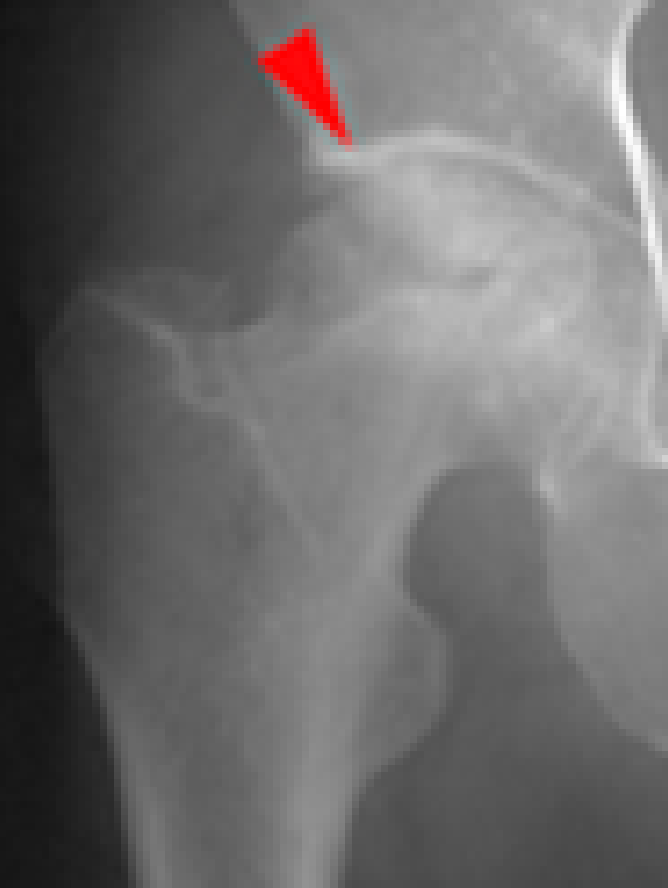

図5. 大腿骨頭壊死症

(赤矢印が骨頭壊死部分)

5. 大腿骨頭壊死症

大腿骨頭壊死症は、大腿骨頭への血流障害によって股関節が破壊される病気で(図9赤矢印)原因は分かっておらず難病指定されています。しかし、ステロイド剤を多量に使用したパルス療法やアルコール多飲歴の有る方に多く発症しやすい傾向があります。

図9. 代替骨頭壊死症(赤矢印が壊死部分)